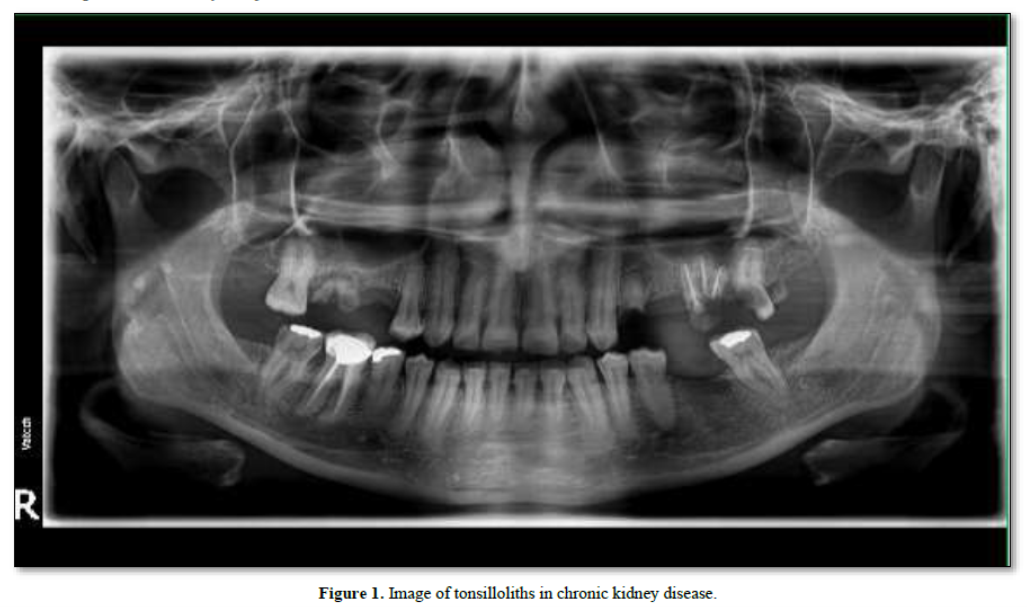

The presence of tonsillar calculi was investigated on panoramic radiographs by two calibrated oral radiologists and a post graduate student based on reported criteria by Takashi [9]. According to this definition, tonsilloliths are numerous small and ill-defined radiopacities located on the ramus or the masses were gathered on the mandible and soft palate and frequently superimposed over the border of the tongue shadow (Figure 1).

Results: In CKD group, three cases (16.6%) had right side, nine (50%) had left side, and six (33.3%) had tonsilloliths on both sides. Four cases (2.85%) of kidney transplant group also had both tonsillar stones and calcified stylohyoid ligament. In normal group, four (57%) of the subjects had both sides, two (28.5%) had right side and one (14.2%) had left side stones. All of the lith sizes were estimated smaller than 5 mm, and most were diagnosed as 2-7 oval, round or irregular particles in shape.

In the normal group, four (57%) of the subjects had both sides, two (28.5%) had right side and one (14.2%) had left side stones. All liths were estimated to be smaller than 5 mm, and most were diagnosed as 2-7 oval, round or irregular particles in shape (Table 1).